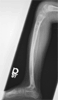

Post Op

Gradual correction using Ilizarov fixator and lengthening

Progress

Correction of deformity and lengthening distal tibia